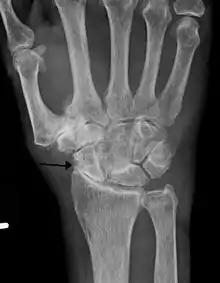

Diagnosis is made with reasonable certainty based on history and clinical examination.[51][52] X-rays may confirm the diagnosis. The typical changes seen on X-ray include: joint space narrowing, subchondral sclerosis (increased bone formation around the joint), subchondral cyst formation, and osteophytes.[53] Plain films may not correlate with the findings on physical examination or with the degree of pain.[54]

X-ray of erosive osteoarthritis of the fingers, also zooming in on two joints with the typical "gull-wing" appearance

Both primary generalized nodal osteoarthritis and erosive osteoarthritis (EOA, also called inflammatory osteoarthritis) are sub-sets of primary osteoarthritis. EOA is a much less common, and more aggressive inflammatory form of osteoarthritis which often affects the distal interphalangeal joints of the hand and has characteristic articular erosive changes on X-ray.[59]